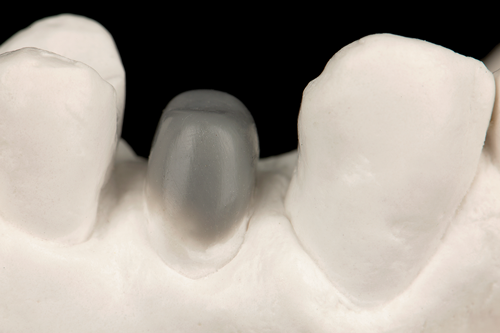

Fig 6. A diagnostic wax-up was fabricated to an ideal coronal preparation geometric shape, dimension, and height for the anticipated final composite core buildup.

Figure 6

Fig 10. Prior to the restorative procedure, a diagnostic wax-up was fabricated to the anticipated extracoronal contours for development of the final crown.

Figure 10